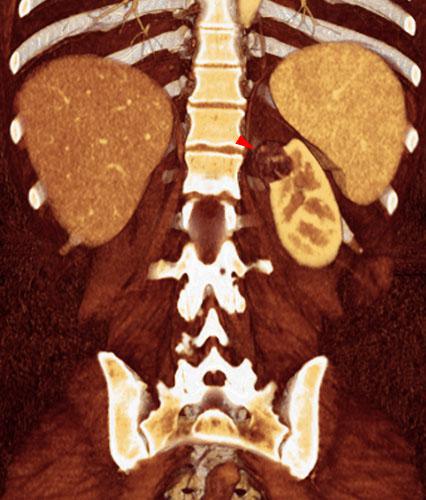

Angiomiolipoma renal 1

VR seccional. Visión coronal anterior. TC contrastado en fase venosa que muestra una lesión cortical en el polo renal superior izquierdo (punta de flecha) heterogénea, con contenido graso, confirmando este diagnóstico